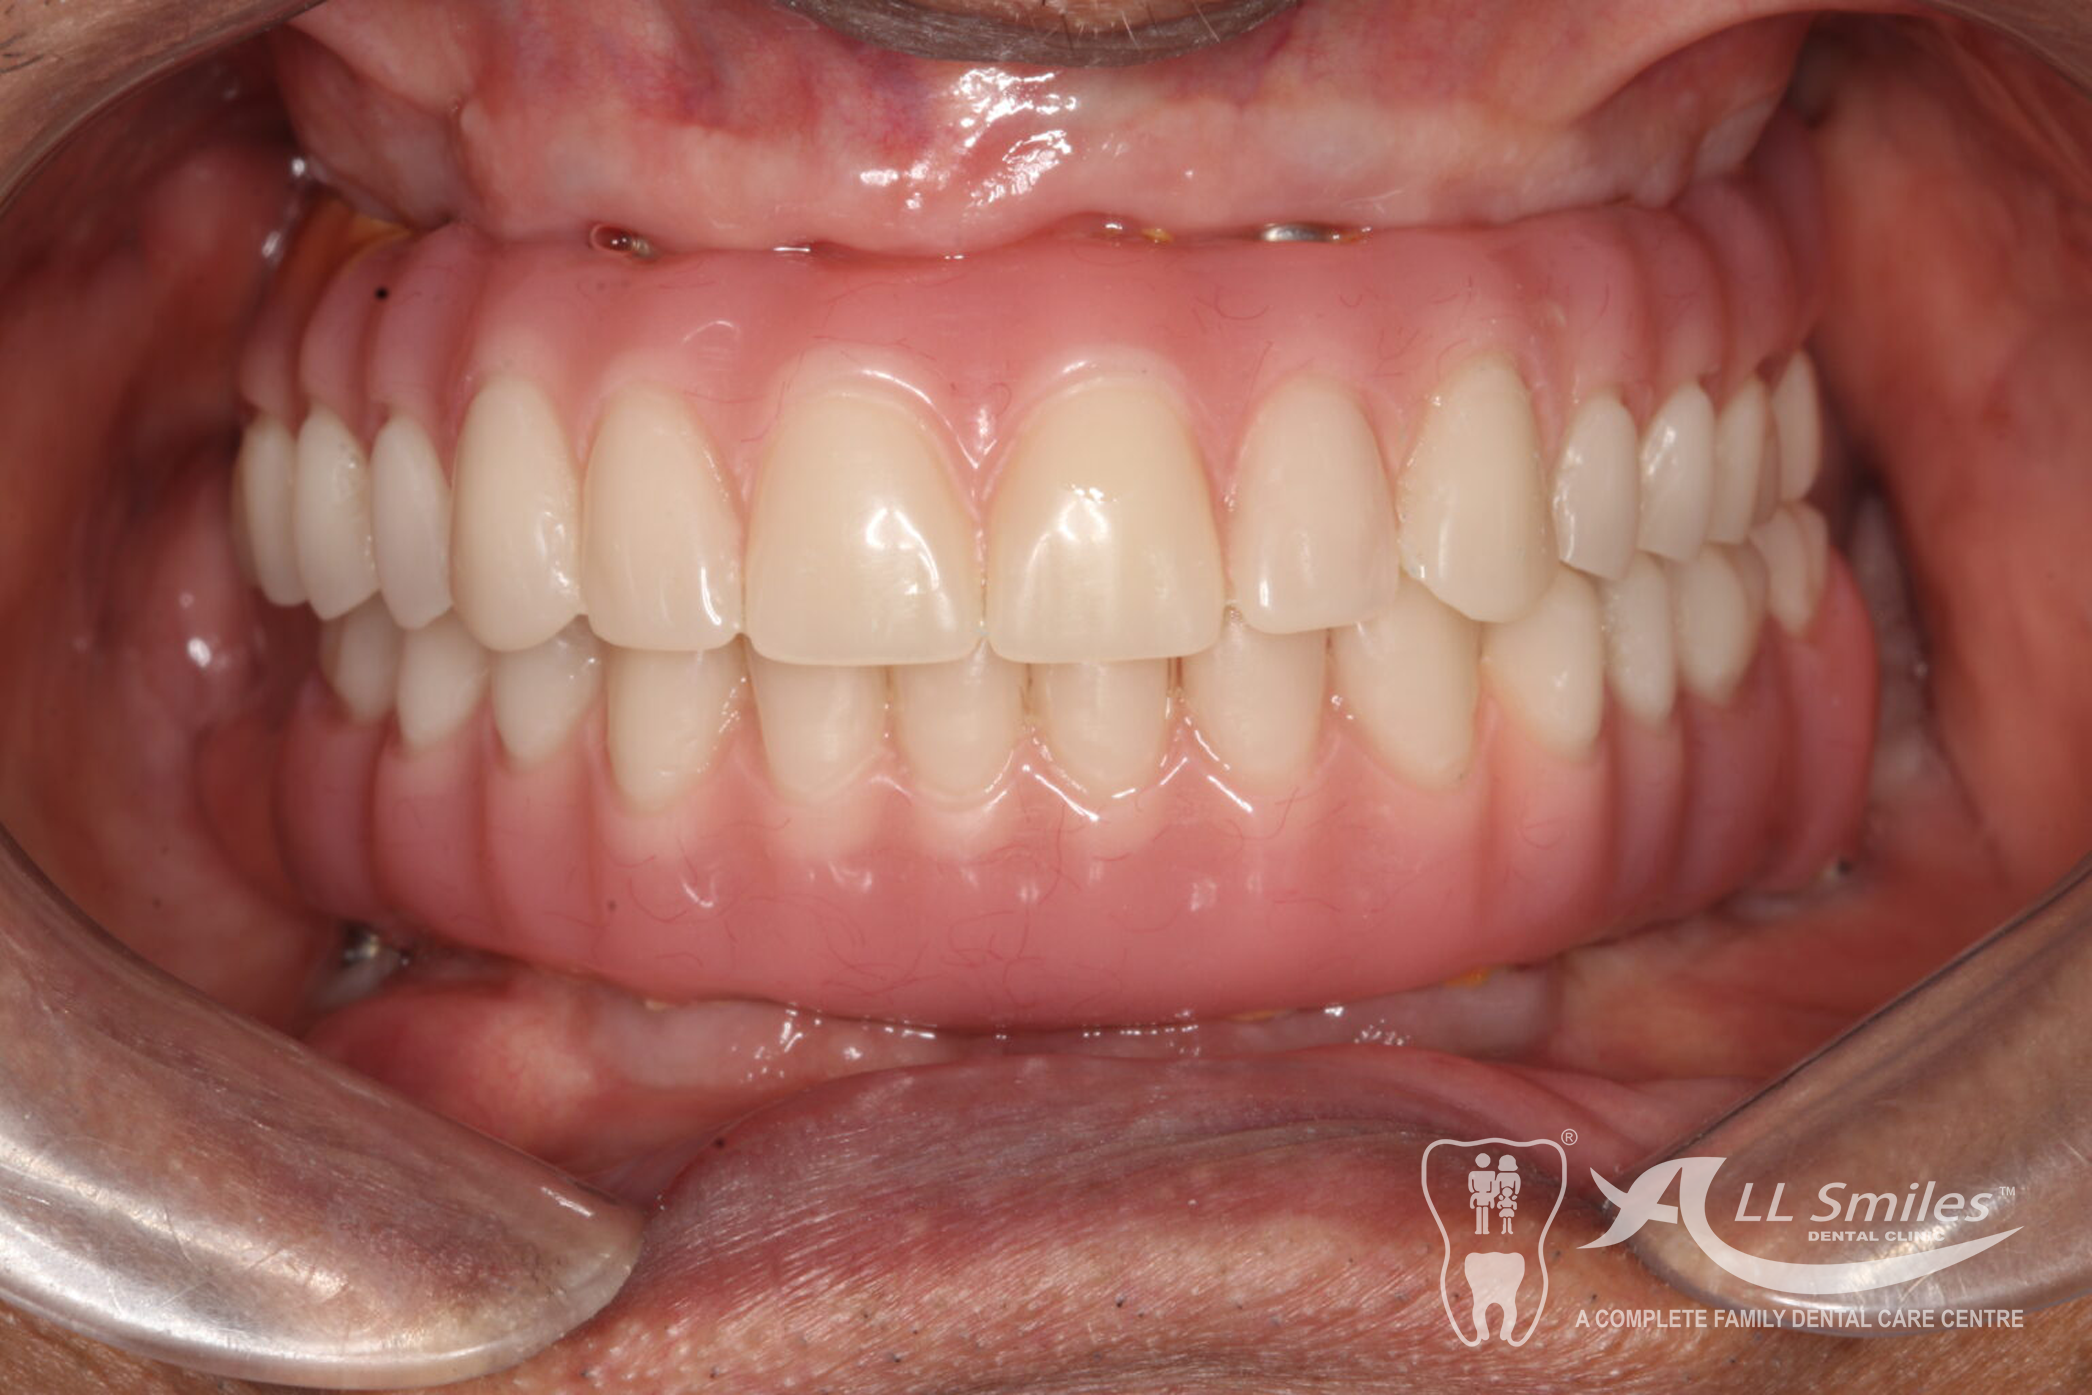

You will still be able to laugh with dental implants. As few as two to four new roots will be enough to provide a firm base for a full denture. A bridge can be fixed to six implants. This will give you a high degree of security in every situation because nothing can come loose unexpectedly. No more embarrassing surprises.

- All on 4 or All on 6: A bridge can be permanently anchored to 4 or 6 implants in your jaw. The Implants for each arch are placed in a single appointment. It is often possible to fix the provisional denture to the new roots at the same time implants are placed in the jaw. You come to the appointment in the practice and leave few hours later with firmly fixed, beautiful teeth. After the healing phase this is replaced by the permanent ceramic or acrylic prosthesis.

A bridge can be permanently anchored to 4 or 6 implants in your jaw. The Implants for each arch are placed in a single appointment. It is often possible to fix the provisional denture to the new roots at the same time implants are placed in the jaw. You come to the appointment in the practice and leave few hours later with firmly fixed, beautiful teeth. After the healing phase this is replaced by the permanent ceramic or acrylic prosthesis.